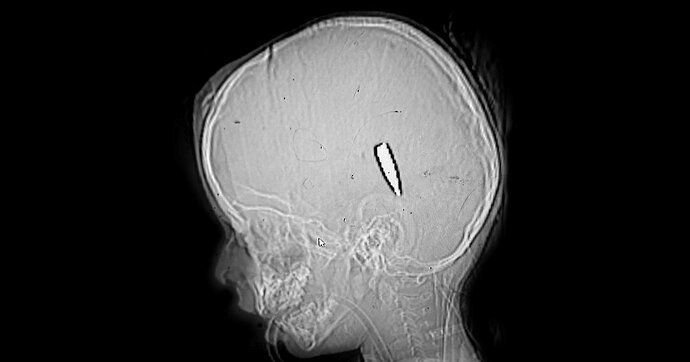

What the wounds are telling us,

Doctors in Gaza observed a disturbing pattern: children with a single gunshot wound to the head or chest, a sign that they had been deliberately targeted. This emerges from research by de Volkskrant, which spoke with the doctors who are among the last international eyewitnesses.